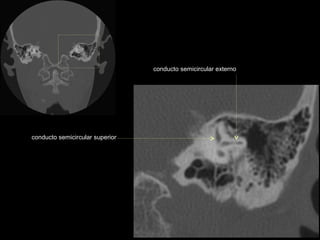

CATEDRA DE RADIOLOGIA U.N.L.P.   Hueso temporal normal              Edición 2002

seno maxilar

conducto

carotídeo

auditivo externo

protuberancia

occipital externa

trompa de Eustaquio

conducto auditivo externo

celdillas mastoideas

eminencia piramidal

seno timpánico

receso del n. facial

nervio facial (3era)

estribo (cruras)

nervio facial

ventana oval

martillo

yunque

cóclea

vestíbulo

conducto semicircular externo

articulación yunque/martillo

conducto auditivo interno

conducto semicircular posterior

antro mastoideo

celdillas retrolaberínticas

conducto semicircular

superior

conducto semicircular superior